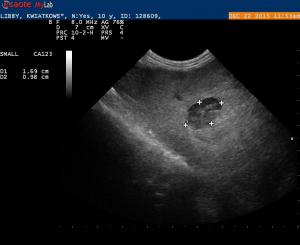

Splenic Lesion

Libby is a 10 year old Cavalier King Charles Spaniel that was in for dental work today. I often place the probe on the abdomen just for practice. While I was taking a quick look at Libby- I noticed a cystic like lesion on the head of the spleen. I would like some feedback- should…